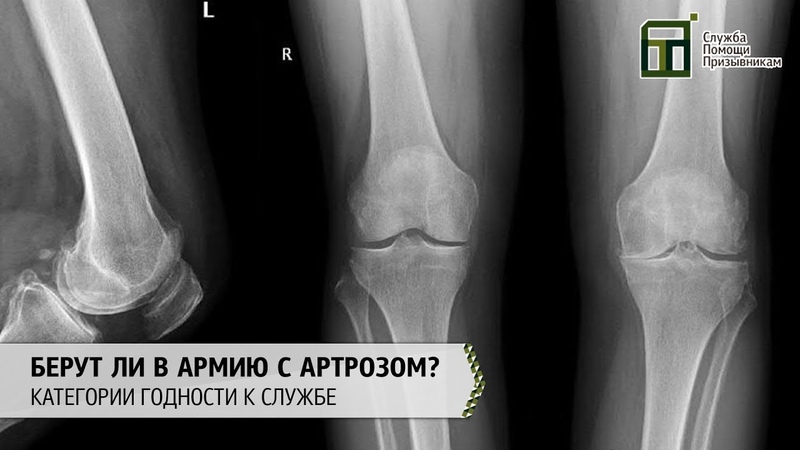

Остеоартроз приводит к деформации сустава различной степени выраженности. В самом начале заболевания этот симптом можно выявить только при рентгенологическом исследовании или при магниторезонансной томографии. Если заболевание будет выявлено на ранних стадиях своего развития, то развитие деформации можно предотвратить или значительно замедлить. Вот почему важно своевременное обращение к врачу!

При диагностике остеоартрита хирург стопы и голеностопного сустава тщательно осматривает стопу на предмет припухлости в суставе, ограничения подвижности и боли при движении.

В некоторых случаях может отмечаться деформация и/или увеличение (шпора) сустава. Для оценки степени заболевания может быть назначен рентген.

Другие тесты могут определить, могут ли другие типы артрита быть причиной болей в лодыжках, такие как анализы крови, которые измеряют воспаление и антитела, чтобы исключить воспалительный артрит, или тестирование суставной жидкости на кристаллы мочевой кислоты при подозрении на подагру.Визуализирующие тесты, такие как рентген, могут помочь подтвердить диагноз и определить степень повреждения сустава.

- Рентген.